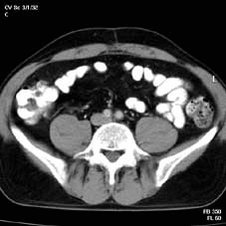

الأشعة المقطعية للبطن 🌟👇🏻

Abdominal CT

⚪️Targets Sign ➡️ indicates intussusception (seen in CT and US)

✳️Less than 15% of patients with intussusception present with the classic triad of abdominal pain, a palpable sausage-shaped abdominal mass, and blood per rectum‼️